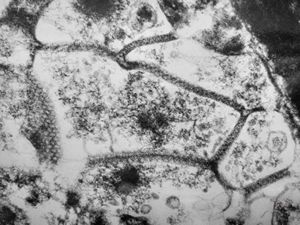

M,41y. | ribosome-lamella complex in tricholeukocyte -hairy cell leukemia, spleen

M,41y. | ribosome-lamella complex in tricholeukocyte -hairy cell leukemia, spleen

M,41y. | ribosome-lamella complex in tricholeukocyte -hairy cell leukemia, spleen